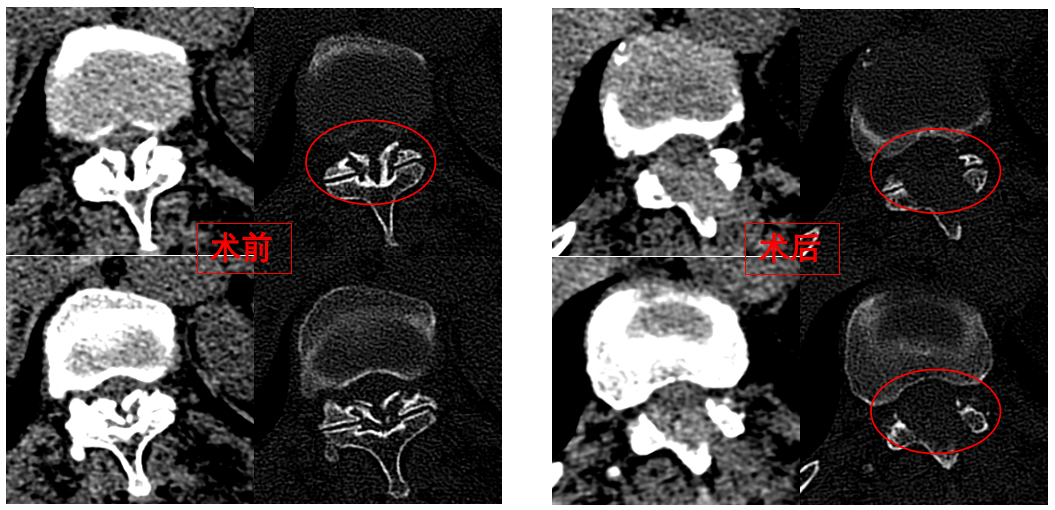

華西醫(yī)院成辦分院骨科副主任醫(yī)師張斌接診后,憑借豐富的脊柱治療經(jīng)驗,立即安排卓瑪阿媽做了系列精密檢查,檢查結(jié)果顯示,阿媽胸椎11/12節(jié)段黃韌帶嚴(yán)重骨化,導(dǎo)致椎管顯著狹窄,脊髓受壓,確診為嚴(yán)重的“胸椎黃韌帶骨化癥”,如果不及時手術(shù)最終可能面臨癱瘓的風(fēng)險。

手術(shù)歷時一個半小時,骨科脊柱微創(chuàng)團(tuán)隊成功完整切除了壓迫脊髓的骨化黃韌帶,徹底解除了卓瑪阿媽的脊髓壓迫。手術(shù)過程順利,手術(shù)切口僅1厘米。

圖為卓瑪阿媽術(shù)前、術(shù)后胸椎CT照片對比。